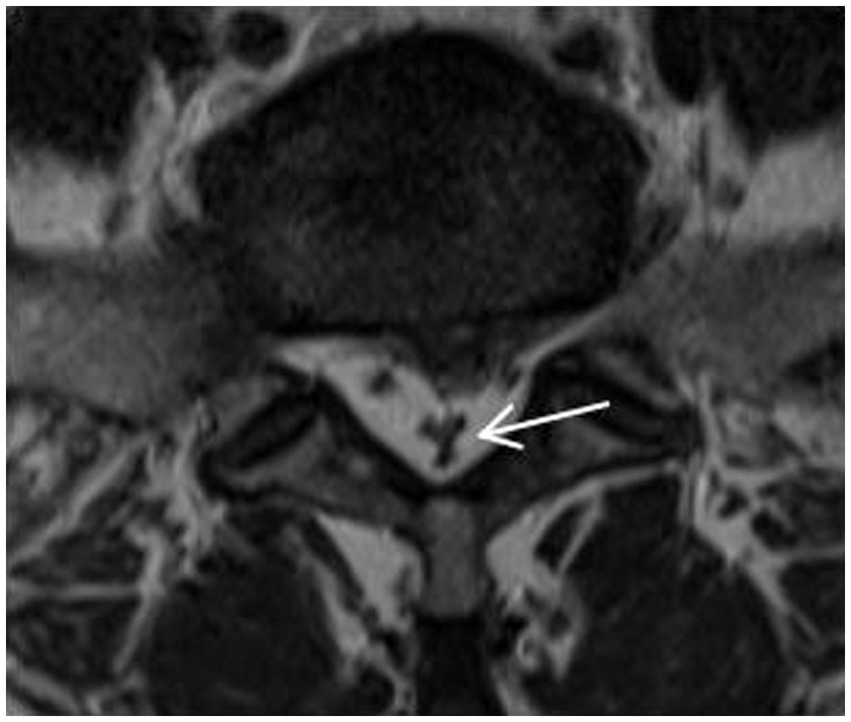

Magnetic resonance imaging (MRI) technology has become a reliable imaging method for the diagnosis of RNRs and LSS due to its good soft tissue resolution, multiparameter measurement, and multisequence and multiplane imaging methods, making it a key player in surgical decision-making. On preoperative magnetic resonance imaging, RNRs show thickening, buckling, and serpentine- or loop-shaped on their T2-weighted sagittal MRI slices (Figure 1), which are often further diagnosed on the basis of a diagnosis of central LSS (14). Magnetic resonance imaging of central lumbar LSS shows a median sagittal diameter of the lumbar spinal canal that is less than 15 mm. The main imaging signs include vertebral body and vertebral small joint osteophytes, vertebral body slippage and instability, disc bulging, disc herniation or calcification due to degeneration and degeneration of the intervertebral disc, and hypertrophy or calcification of the ligamentum flavum. The above imaging method facilitates comprehensive analysis of the vertebral body itself and the surrounding tissue anatomy, and the epidural fat is an important soft tissue that maintains the vertebral body structure and movement. Tissue imaging study of other surrounding organs has received increasing attention. For example, perirenal fat thickness (PFT) is highly correlated with renal trauma grade (15), but it is often neglected in the imaging diagnosis of LSS patients and has not been reported. In magnetic resonance imaging studies of LSS combined with RNRs (6, 13, 16–18), it was shown that the sagittal and transverse diameters of the spinal canal at the level of maximal stenosis, the area of the dural sac, the thickness of the ligamentum flavum, and the presence or absence of disc herniation and lumbar spondylolisthesis contributed to the development of RNRs, and it was concluded that for female patients, the older they were, and the higher the degree of lumbar canal stenosis, the more likely they were to develop RNRs. Studies evaluating cause and occurrence have shown that patients with thickening and hypertrophy of the ligamentum flavum and lumbar spondylolisthesis have a higher chance of developing RNRs. However, the studies are not comprehensive; for example, the correlation between the condition of epidural fat and RNRs has not been reported, while the early diagnosis of RNRs, i.e., the use of different causes in predicting the occurrence of RNRs, has not been reported.

Figure 1

RNRs show thickening, buckling, and serpentine- or loop-shaped on their T2-weighted sagittal MRI slices.